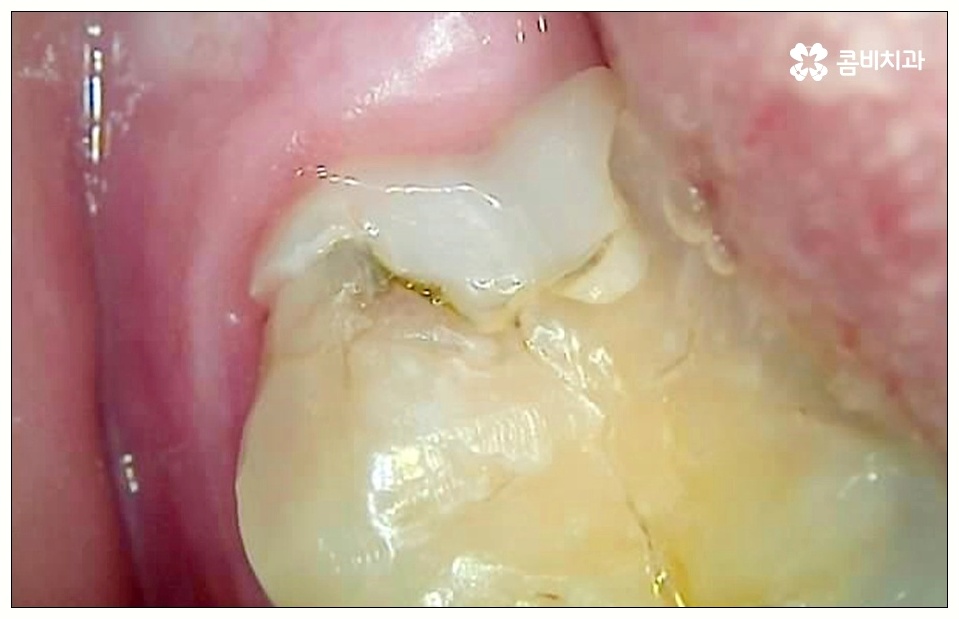

이렇게 병증이 깊어지게 되면 치은에도 쉽게 손상이 일어나고 치아 내부 밀도가 떨어져 치아 파절이 일어날 수 있으며 결국 사랑니만 뽑는 것이 아니라 저작 기능에 중요한 역할을 하는 어금니까지 발치해야 하는 상황이 생길 수도 있기 때문에 초기에 잘 대처하실 필요가 있어요.

치아 사이 충치는 법랑질이 두꺼운 교합면, 즉 음식을 잘게 부수는 윗면이 아니라 치아와 치아 사이에 맞닿고 있어 비교적 법랑질의 두께가 얇고 신경까지의 거리가 짧은 옆면에 생기는 것이기 때문에 병증이 진행되는 속도가 빠르고 치료하기가 까다로워 될 수 있는대로 빨리 대처하실 필요가 있어요.

사랑니로 인해 어금니 사이 충치 가 발생하고 치아 파절이 일어나 신경까지 손상이 일어난 경우 원인이 된 사랑니를 발치한 후에 신경 치료와 크라운 처치를 통해 어금니 수복을 해 주게 되는데 이 때 근관 소독 및 밀봉 후 통증이 없어졌다고 해서 크라운 처치를 해 주지 않은 채로 치료를 마치게 되면 2차 감염이 일어나거나 외부 충격으로 인해 또 다시 파절이 생길 가능성이 높아 어렵게 살린 어금니를 잃게 될 수도 있으니 꼭 남아 있는 치아를 전체적으로 덮어주는 크라운 처치를 통해서 보호해 주시는 것을 권유드리고 있습니다.